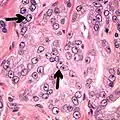

This case could meet the criterion of six times normal nuclear size for intraductal carcinoma of the prostate if size is defined as nuclear area but not if defined as nuclear diameter (blue dot: size of normal nucleus, green dot: size six times normal area and red dot: size six times normal diameter).[19]

Intraductal carcinoma of the prostate gland (IDCP), which is now categorised as a distinct entity by WHO 2016, includes two biologically distinct diseases. IDCP associated with invasive carcinoma (IDCP-inv) generally represents a growth pattern of invasive prostatic adenocarcinoma while the rarely encountered pure IDCP is a precursor of prostate cancer.[19] The diagnostic criterion of nuclear size at least 6 times normal is ambiguous as size could refer to either nuclear area or diameter. If area, then this criterion could be re-defined as nuclear diameter at least three times normal as it is difficult to visually compare area of nuclei.[19] It is also unclear whether IDCP could also include tumors with ductal morphology.[19] There is no consensus whether pure IDCP in needle biopsies should be managed with re-biopsy or radical therapy. A pragmatic approach would be to recommend radical therapy only for extensive pure IDCP that is morphologically unequivocal for high-grade prostate cancer.[19] Active surveillance is not appropriate when low-grade invasive cancer is associated with IDCP, as such patients usually have unsampled high-grade prostatic adenocarcinoma.[19] It is generally recommended that IDCP component of IDCP-inv should be included in tumor extent but not grade.[19] However, there are good arguments in favor of grading IDCP associated with invasive cancer.[19] WHO 2016 recommends that IDCP should not be graded, but it is unclear whether this applies to both pure IDCP and IDCP-inv.[19]